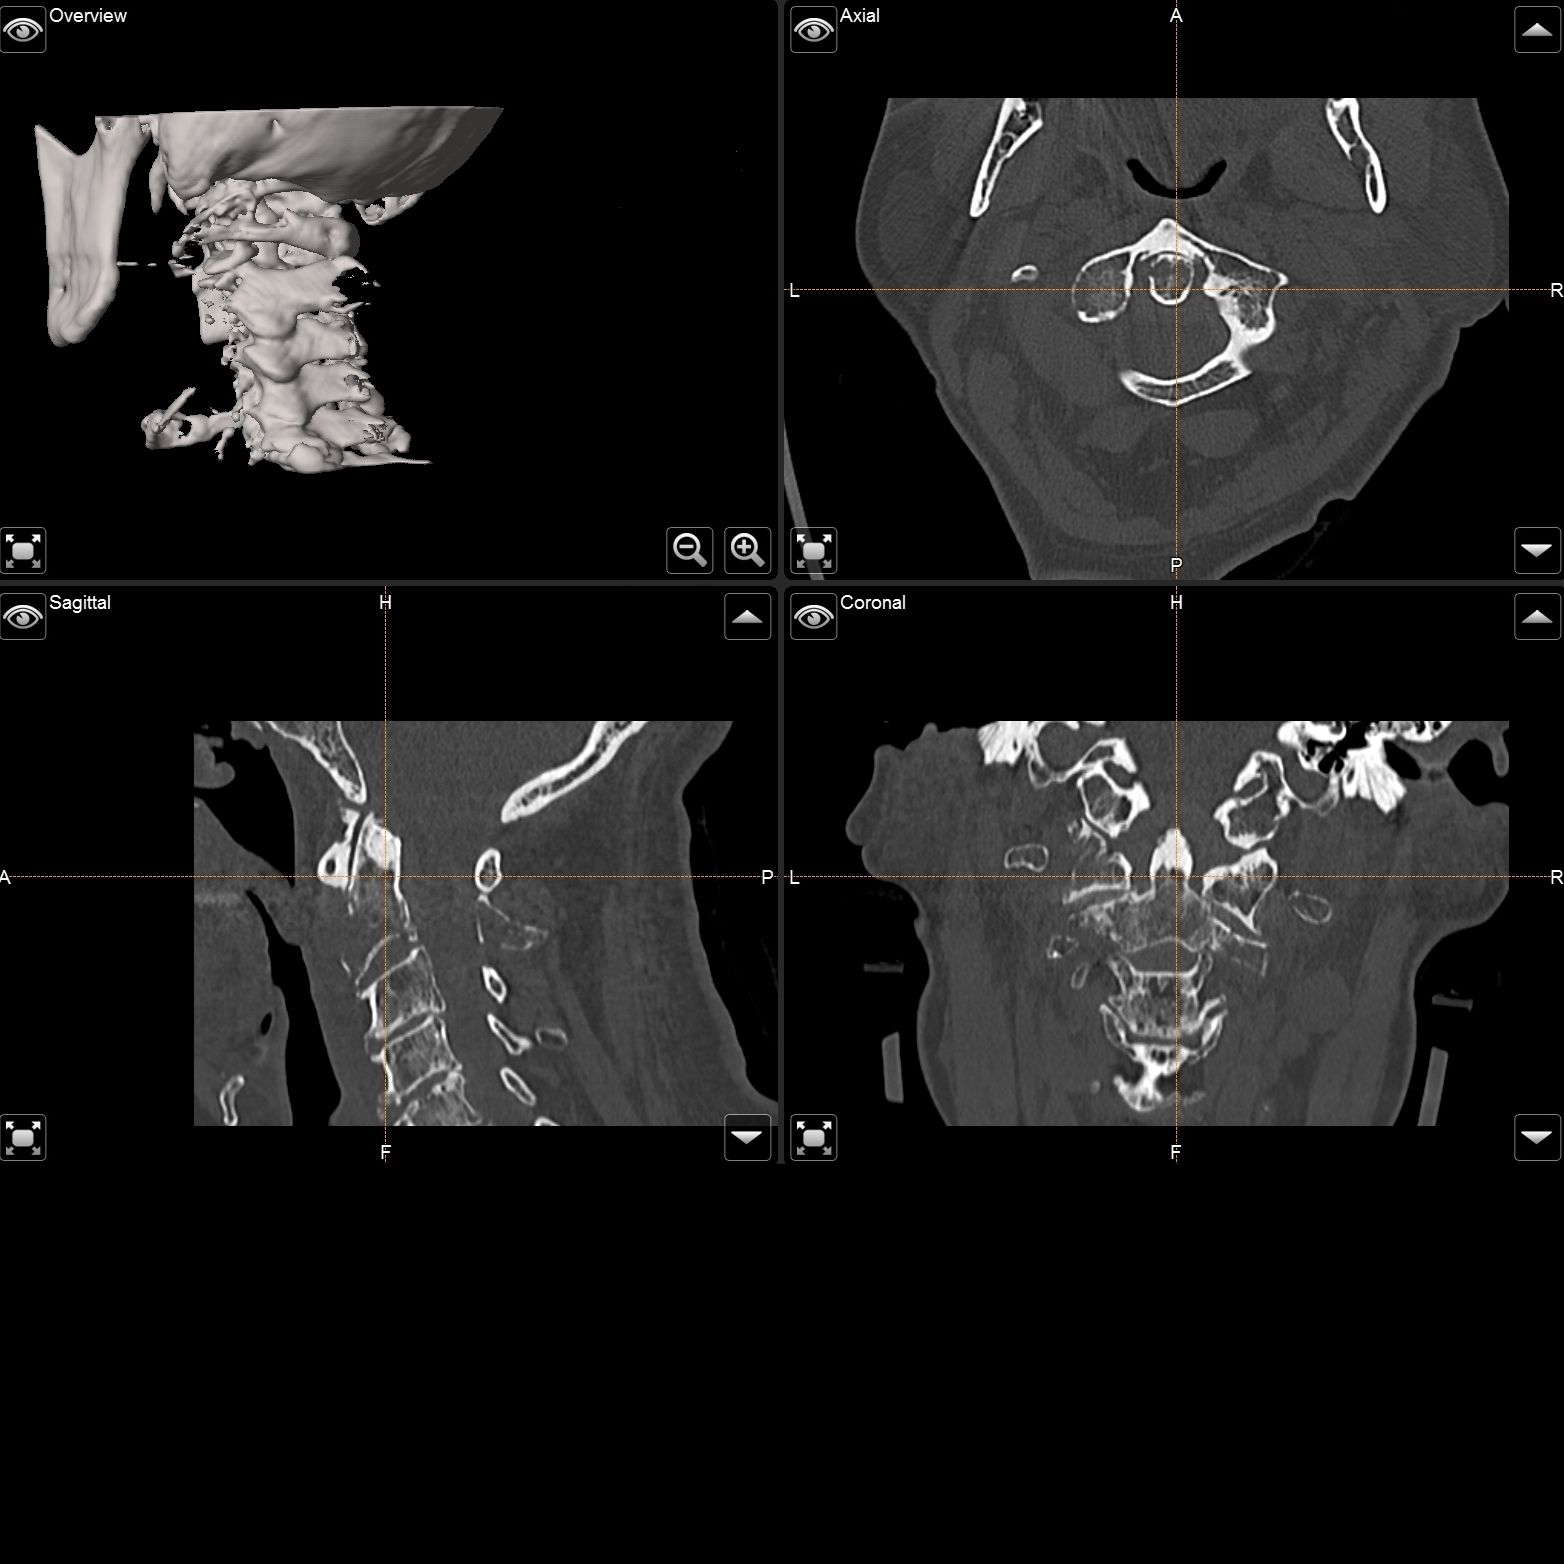

Intraoperativer Röntgen C-Bogen mit 3D Rekonstruktion

Intraoperativer Röntgen

C-Bogen mit

3D Rekonstruktion

Die Universitätsklinik Tübingen verfügt über hochmoderne mobile Bildgebungssysteme, darunter der robotisch geführte digitale Volumentomograph Loop-X der Firma Brainlab sowie ein mobiler 3D-C-Bogen der Firma Ziehm. Diese fortschrittlichen Systeme ermöglichen intraoperativ eine präzise 3D-Rekonstruktion des Kopfes oder der Wirbelsäule. Für die Kopf- und Wirbelsäulenchirurgie kann mithilfe dieser Technologien ein Navigationsdatensatz erstellt werden, der eine hochpräzise Navigation gewährleistet. So können beispielsweise Schrauben in der Wirbelsäule exakt platziert und kontrolliert oder Trajektorien für Zugangswege und Probenentnahmen im Kopf definiert werden.